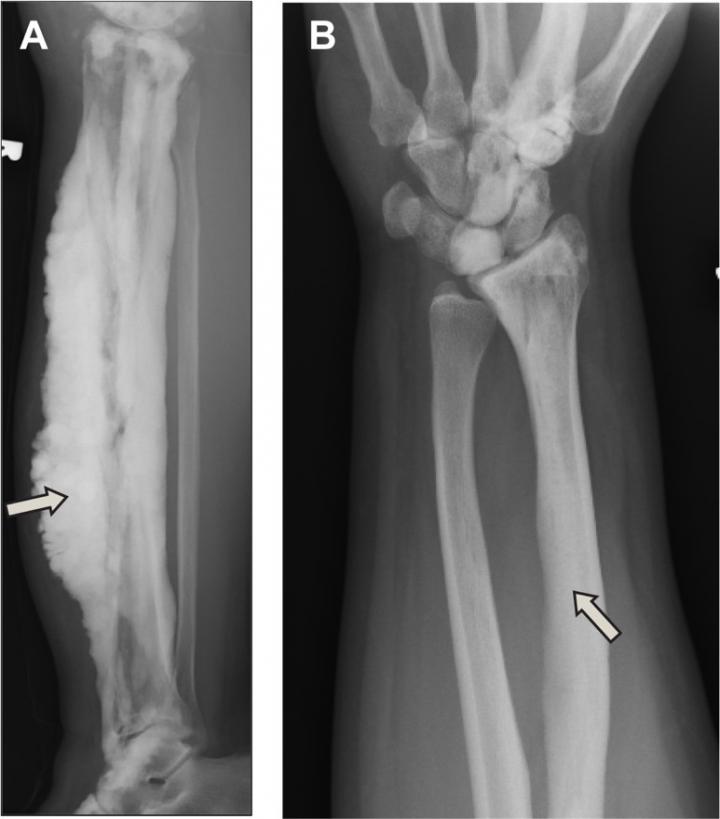

image: At left, a bone with the dripping candle wax form of melorheostosis; at right, a bone with melorheostosis resulting from a mutation in the SMAD3 gene.

Researchers at the National Institutes of Health have discovered a second gene that causes melorheostosis, a rare group of conditions involving an often painful and disfiguring overgrowth of bone tissue. The gene, SMAD3, is part of a pathway that regulates cell development and growth. The researchers are now working to develop an animal model with a mutant version of SMAD3 to test potential treatments for the condition. The study appears in the Journal of Experimental Medicine.

Melorheostosis affects about 1 in 1 million people. Its causes have long been unknown. DNA tests of blood and skin could not identify a mutation. The key to finding the gene was to biopsy the affected bone directly and compare it to unaffected bone. Earlier, the researchers used this method to discover the gene for "dripping candle wax bone disease," a form of melorheostosis in which excess bone growth appears to drip from the bone surface like hot wax. In that study, mutations in the gene MAP2K1 accounted for eight cases of the disease among 15 patients.

The researchers found SMAD3 mutations in four of the patients who did not have mutations in MAP2K1. SMAD3 is involved in a pathway crucial for skeletal development both before and after birth. The SMAD3 mutations increase the maturation of bone-forming cells and are involved in a cellular pathway distinct from the MAPK2K1 pathway.